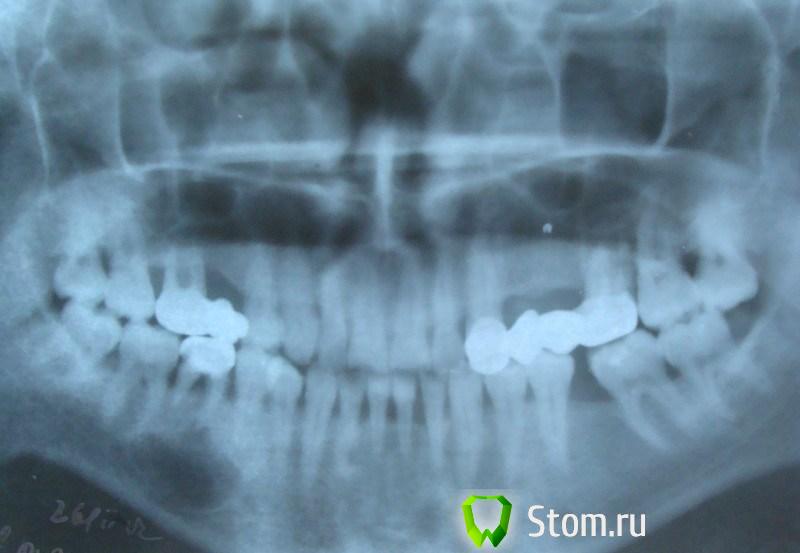

светляк Опубликовано 15 января, 2012 Поделиться Опубликовано 15 января, 2012 Здравствуйте,коллеги.Не знаю,можно ли назвать экспериментом мой случай или все-таки желание сохранить зуб...: Молодая девушка. Зуб 46-резорциненный-не беспокоил,но коронковая часть разрушена почти полностью(если не учитывать старую ,ужасную пломбу без намека на всякую анатомию).На снимке-резорбция медиальных корней.Конечно,с моей стороны последовало предложение удалить зуб и не рисковать,но пациентка пожелала рискнуть("удалить всегда успею"). И с согласия пациентки со всякими расписками о безгарантийном лечении мы начали лечение,которое продолжалось где-то 4 месяца.Была проведена эндодонтия,заложен каласепт и меняла я кала септ на протяжении лечения 3 или 4 раза.Через 4 месяца,увидев,что разрежение уменьшилось,я запломбировала каналы окончательно.Затем-культевая вкладка и коронка. Вложения-приличные.Но иначе восстановить не получилось бы. Ссылка на комментарий

светляк Опубликовано 15 января, 2012 Поделиться Опубликовано 15 января, 2012 Коллеги,извините,за качество.Ну не очень я дружу с отправкой снимков... Смотреть снимки надо в такой последовательности: 1-5-6-2-3-4. Ссылка на комментарий

светляк Опубликовано 15 января, 2012 Поделиться Опубликовано 15 января, 2012 Хотела понаблюдать,будет ли положительная динамика,поскольку культевая+м/к -недешевое удовольствие.Плюс ко всему,после распломбировки он дал обострение,думала удалять придется...Но ,обошлось. Ссылка на комментарий